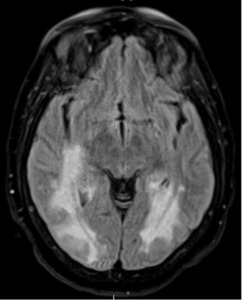

The diagnosis of PML was based on magnetic resonance imaging (MRI) findings and clinical presentation, including progressive vision loss and neurological decline. Prior to her hospitalization, an outpatient brain MRI revealed extensive T2/FLAIR hyperintensities in the parieto-occipital white matter and splenium of the corpus callosum, concerning for PML (Image 1).

A repeat inpatient brain MRI consistently indicated PML, displaying mild progression of the extensive abnormal signal without significant mass effect or enhancement. A lumbar puncture revealed cerebrospinal fluid with 3,100,000 copies/mL of JC virus, confirming the diagnosis.

While MRI findings were also consistent with Posterior Reversible Encephalopathy Syndrome (PRES), this was less likely. Immune Reconstitution Inflammatory Syndrome (IRIS) was ruled out due to the lack of imaging enhancements typical of IRIS and the onset of symptoms prior to ART reinitiation.